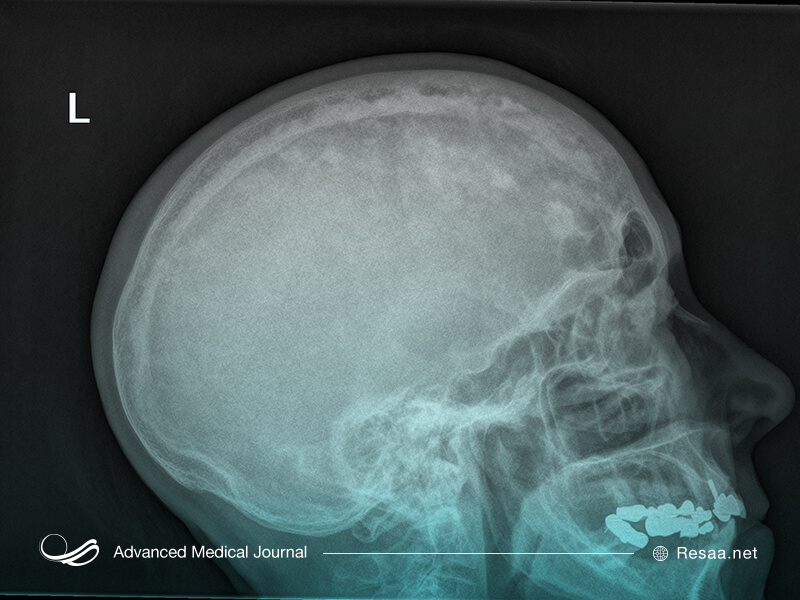

- جمجمه

اگر استخوان شما به روشی نادرست تغییر یافته باشد، پزشک ممکن است بتواند بیماری شما را از نظر علائم و معاینه جسمی تشخیص دهد اما معمولاً برای تأیید آن به پرتو نگاری و آزمایش خون احتیاج دارید. حتی اگر علائم واضحی نداشته باشید، برخی نتایج آزمایشهای خون به بیماری پاژه اشاره میکنند.

- ناشنوایی. اگر استخوانهای سر شما تحت تأثیر قرار گرفته باشند، ممکن است منجر به از بین رفتن شنوایی یا ناشنوایی کامل شود. به نظر میرسد این عارضه به دلیل ضخیم شدن استخوانهای اطراف گوش شما ایجاد میشود.